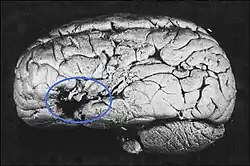

Was Broca einen Platz in der Medizingeschichte sichert, ist seine 1861[6] publizierte Entdeckung des Sprachzentrums im Gehirn, heute bekannt als Broca-Areal, gelegen im dritten Gyrus (Gehirnwindung) des Frontallappens der linken Gehirnhälfte.

Er studierte um das Jahr 1860 Patienten mit einer Aphasie (Sprachstörung mit Verlust der Fähigkeit, Wörter hervorzubringen oder zu verstehen[7]). Sein erster Patient namens Leborgne im Pariser Hôpital Kremlin-Bicêtre konnte nur noch die Silbe ‚Tan‘ aussprechen, weswegen er den Spitznamen „Tan“ erhielt. Das Sprachverständnis dagegen schien nicht beeinträchtigt zu sein: Er war durchaus noch in der Lage, ihm gestellte Fragen zu verstehen. Durch prosodische Artikulation verschiedener Betonungsmuster, Tonhöhen und Aneinanderreihungen dieser einen Silbe versuchte „Monsieur Tan“ die Fragen zu beantworten. Die Autopsie und Untersuchung des Gehirns durch Broca ergab, dass ein Teil der linken Gehirnhälfte zwischen dem Frontallappen und dem Temporallappen eine neurosyphilitische Läsion aufwies. Er berichtete 1861 auch über einen weiteren Patienten, der ebenfalls einen fast völligen Sprachverlust (von Broca „Aphemia“ genannt)[8] erlitten hatte.

Broca folgerte daraus, dass diese Stelle maßgeblich an der Sprachproduktion beteiligt sein müsse. Aus Brocas Befunden entstand die Vorstellung der Lateralisation, also der „asymmetrischen Repräsentation bestimmter Funktionen im Gehirn“.[9]